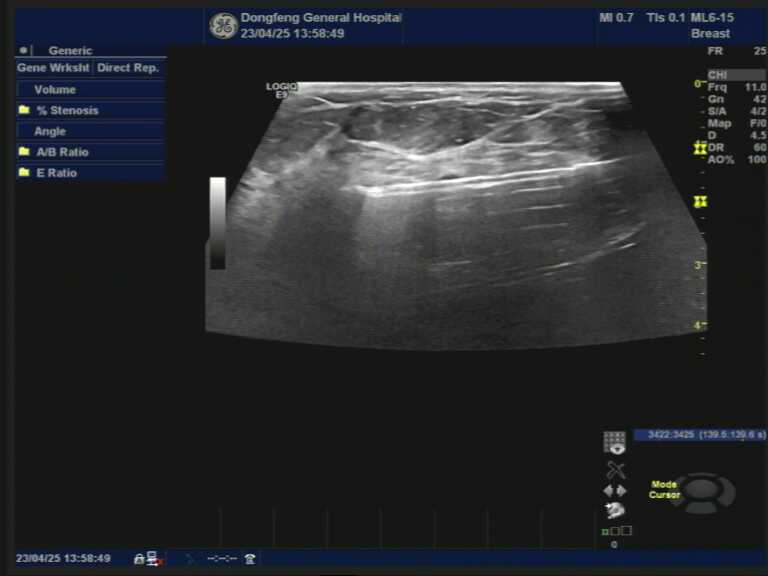

“乳”此美丽,快乐生活

说到乳腺手术,大部分人都会觉得很恐惧,毕竟乳腺手术需要承担很多,包括身体上的和心理上的。现在解决这个难题的利器来了,乳腺旋切术,也称为真空辅助乳腺活组织检查(VAB… 详细>>